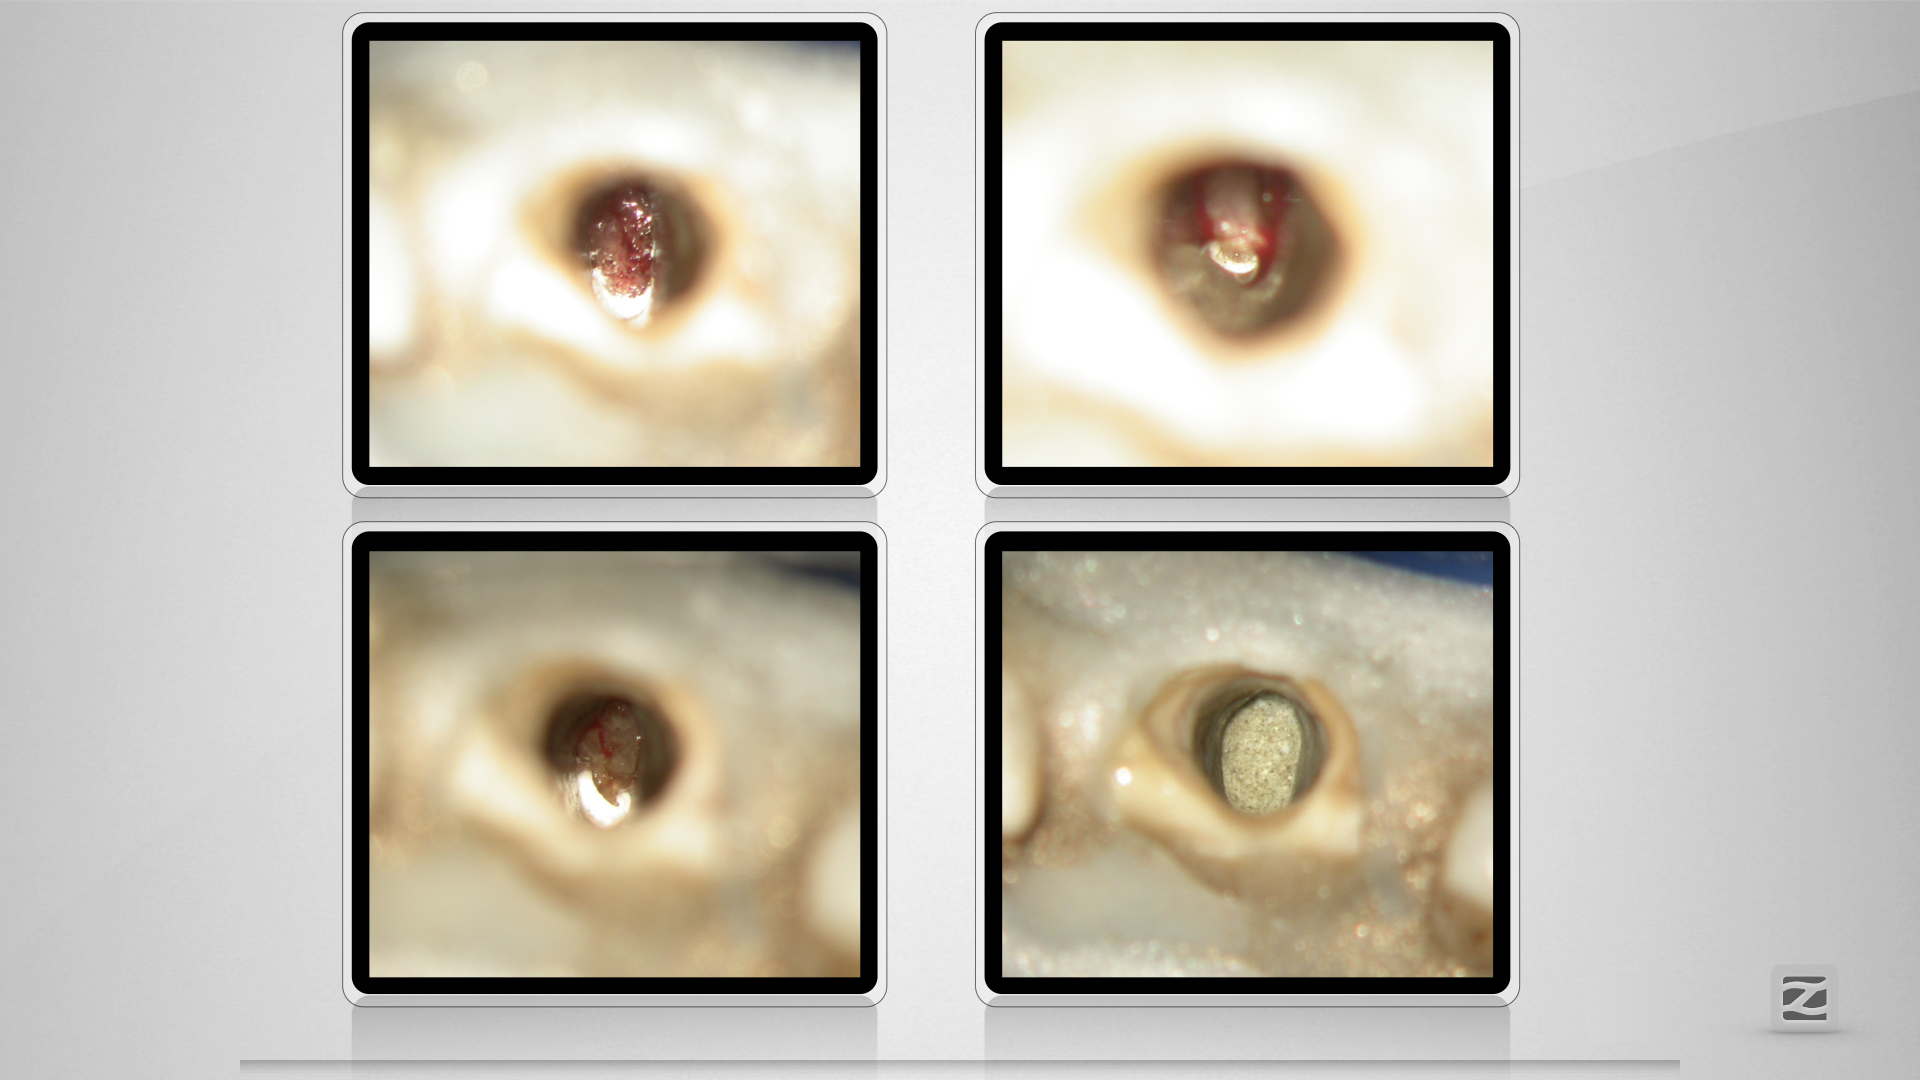

McFly! Jemand zuhause?